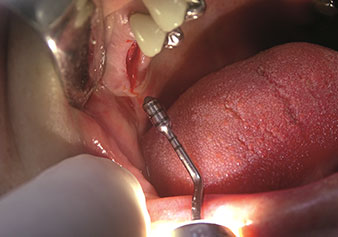

W&H also offers the perfect solution for the internal sinus lift.

Following preparation of the maxillary sinuses with the corresponding instrument set (Fig. 3), the new Z35P instrument (Fig. 4) is used to lift the membrane hydrodynamically. The same instrument set can also be used for piezosurgical preparation of the implant bed in increasing diameters (Figures 3 and 4 included with the kind permission of Dr Mario Kirste, Frankfurt/Oder).

Preparation of implant bed with I4P instrument

Fig. 3: Preparation of implant bed with I4P instrument. Photo: © Dr Mario Kirste (Frankfurt / Oder)